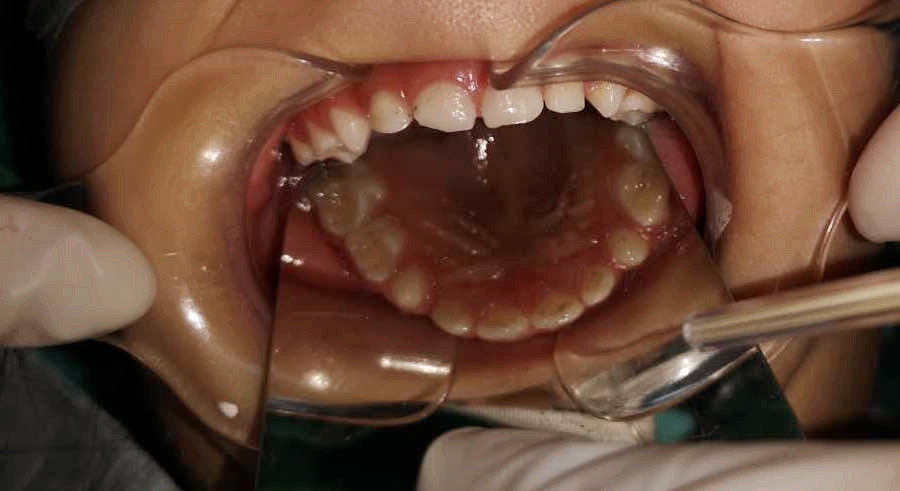

調(diào)節(jié)后

齲齒充填、根管調(diào)節(jié)、窩溝封閉......西海岸新區(qū)中心醫(yī)院的兒童口腔醫(yī)生丁彬主治醫(yī)師和申家麗住院醫(yī)師有條不紊地進(jìn)行著操作,劉亞芳醫(yī)師、李雪飛醫(yī)師和高聰醫(yī)師在旁邊配合著操作,一切井然有序,只有儀器發(fā)出“嘀、嘀”的聲音,提醒著時(shí)間的流逝。

兩個(gè)多小時(shí)后,這一多達(dá)8顆患牙的復(fù)雜調(diào)節(jié)順利完成。在這期間,鑫鑫的心率和血壓一直被密切監(jiān)測(cè)著,一切都很正常。